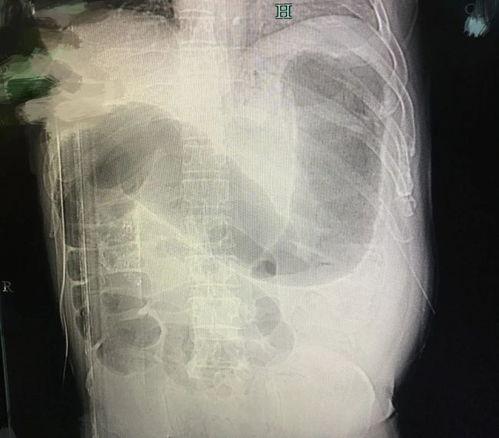

小李赶紧上网查了发现自己可能是吃出了“肠梗阻”。这可把他吓坏了,赶紧去了医院。医生经过检查,确认了小李的病情,告诉他这是由于吃瓜过多,导致肠道堵塞。

说起肠梗阻,可能很多人都不太了解。其实,肠梗阻就是肠道被某种物质堵塞,导致肠道内容物无法正常通过。而吃瓜,竟然也能成为肠梗阻的“元凶”,这究竟是怎么回事呢?

首先,我们要知道,瓜类食物中含有大量的水分和纤维素。这些成分在正常情况下对人体是有益的,但过量摄入,尤其是消化系统功能较弱的人,就可能导致肠道无法正常吸收,从而引发肠梗阻。

其次,瓜类食物在消化过程中会产生大量的气体。这些气体在肠道中积聚,可能导致肠道扩张,进而引发肠梗阻。